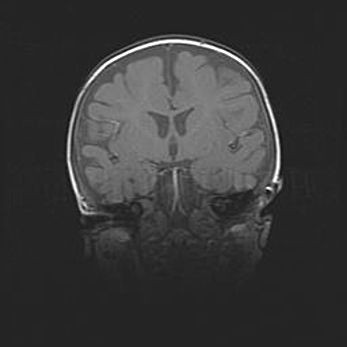

Наружная гидроцефалия с возможной атрофией височных областей.

Возраст: 28 дней

Вес: 3670 г

Пол: мужской

Окружность головы: 38 см

Срок гестации: 40 недель

Гидроцефалия головного мозга у новорожденных – это заболевание, которое характеризуется скоплением избыточного количества спинномозговой жидкости в желудочковой системе головного мозга в результате затруднения её перемещения от места выработки к месту поглощения в кровеносную систему или вследствие нарушения абсорбции. При открытой наружной форме гидроцефалии у новорожденных расширяются и переполняются субарахноидные пространства.

При нормотензивных  формах,  которые,  как  правило,  являются  следствием  перенесенных ишемических  повреждений  паренхимы  мозга,  возможно  сочетание микроцефалии  с нормотензивной гидроцефалией. В основе данных изменений лежит атрофия больших полушарий с преимущественной  локализацией  в  лобно-височных  областях.